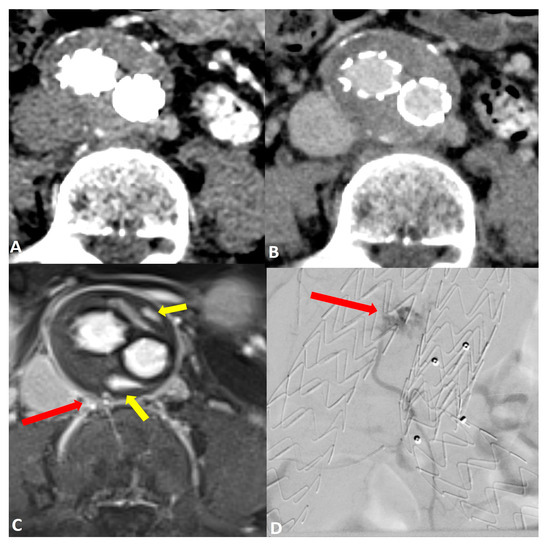

Figure 2.

Post-operative imaging of a 57-year-old woman who underwent endovascular aneurysm repair (EVAR) of the abdominal aorta. Axial CT angiograms in (A) the post-contrast arterial phase and (B) the delayed phase did not reveal a clear endoleak within the growing aneurysm sac. Axial dynamic imaging utilizing the GRASP-VIBE sequence (C) revealed a type II endoleak with the right iliolumbar artery directly communicating with the aneurysm sac, denoted by a red arrow. Notably, there was an accumulation of contrast material at the anterior and posterior peripheral aspects of the aneurysm sac, marked by yellow arrows. This endoleak was subsequently confirmed in the digital subtraction angiography ((D), red arrow) and was promptly treated.